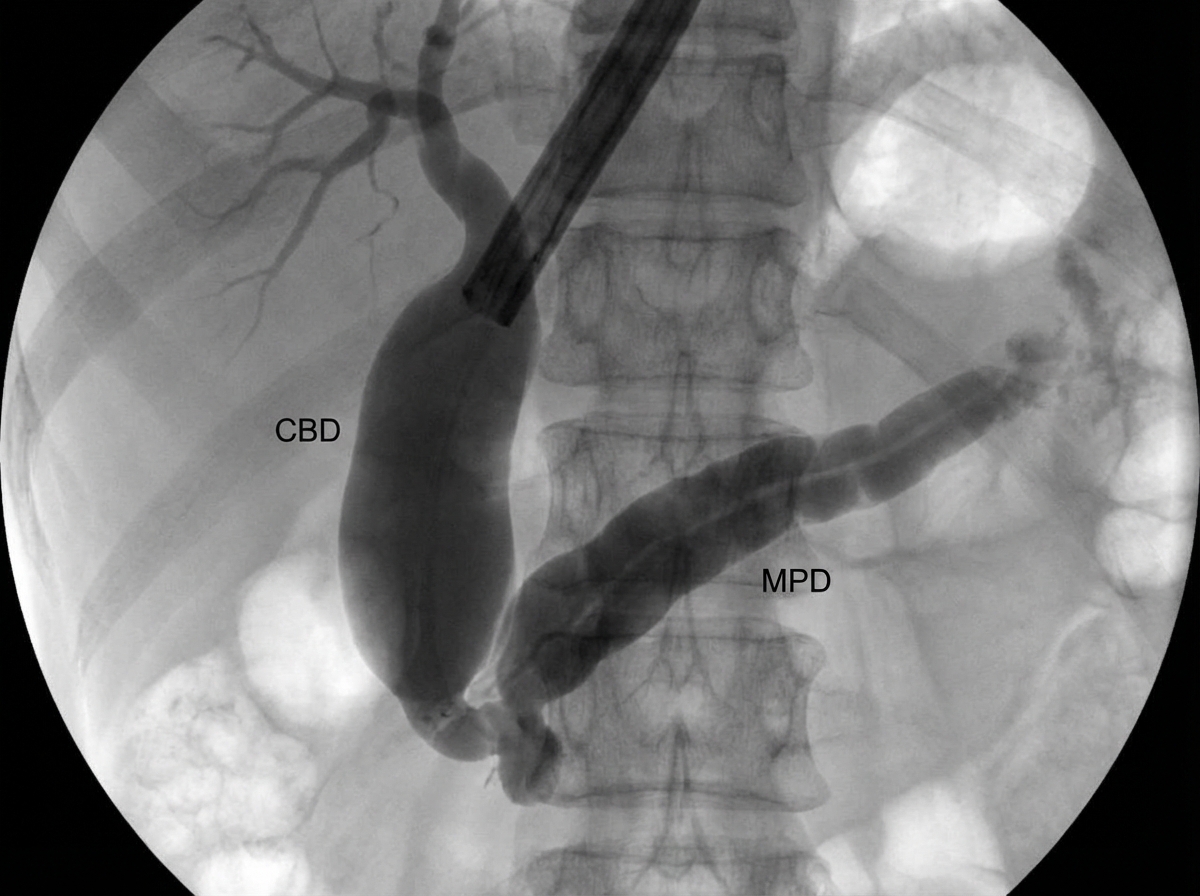

A 60-year-old chronic smoker presented with jaundice, anorexia, and weight loss. ERCP was performed. What is the most likely diagnosis based on ERCP findings?

Explanation: ***Carcinoma of the pancreas*** - **Double duct sign** on ERCP (simultaneous dilation of common bile duct and main pancreatic duct) is pathognomonic for **carcinoma of the head of pancreas**. - Clinical triad of **painless obstructive jaundice**, **weight loss**, and **smoking history** strongly suggests pancreatic adenocarcinoma. *Choledochal cyst* - ERCP would show **cystic dilation** of the bile duct, typically presenting in **childhood or young adults**. - Associated with **choledochal-pancreatic malunion** and **recurrent cholangitis**, not the typical presentation described. *Cholangiocarcinoma* - ERCP typically shows **strictures** and **irregular narrowing** of bile ducts with **beading appearance**. - Usually presents with **cholangitis** and **pruritus** rather than the classic pancreatic cancer triad. *Chronic pancreatitis* - ERCP shows **chain of lakes appearance** with alternating **strictures and dilatations** of the pancreatic duct. - Typically presents with **chronic abdominal pain**, **diabetes mellitus**, and **steatorrhea** rather than painless jaundice.

Explanation: ### Explanation The diagnosis of pancreatic head cancer relies on identifying both the mass and its effect on the biliary and pancreatic ducts. **Why ERCP is the Correct Answer:** In the context of traditional surgical teaching and specific NEET-PG patterns, **ERCP** is considered a superior diagnostic modality for lesions in the head of the pancreas because of its high sensitivity in detecting ductal changes. It can demonstrate the pathognomonic **"Double Duct Sign"** (simultaneous dilatation of the common bile duct and the main pancreatic duct), which is highly suggestive of a head of pancreas malignancy. Furthermore, ERCP allows for tissue acquisition via brush cytology or biopsy and provides a therapeutic window for stenting in patients with obstructive jaundice. **Analysis of Incorrect Options:** * **Ultrasound (A):** Often the initial screening tool, but it is frequently limited by overlying bowel gas and has low sensitivity for small tumors (<2 cm). * **CAT Scan (C):** While **Contrast-Enhanced CT (CECT)** is the gold standard for **staging** and assessing resectability (evaluating vascular invasion), ERCP is traditionally prioritized in exams for its diagnostic precision regarding ductal anatomy in head lesions. * **PTC (D):** An invasive procedure used primarily when ERCP fails or when there is high biliary obstruction. It does not visualize the pancreatic duct. **High-Yield Clinical Pearls for NEET-PG:** * **Gold Standard for Staging:** Triple-phase Contrast-Enhanced CT (CECT). * **Most Common Presentation:** Painless progressive obstructive jaundice. * **Tumor Marker:** CA 19-9 (used for monitoring recurrence, not for primary diagnosis). * **Courvoisier’s Law:** In a patient with obstructive jaundice, if the gallbladder is palpable, the obstruction is unlikely to be due to a stone (points towards malignancy like pancreatic head cancer).